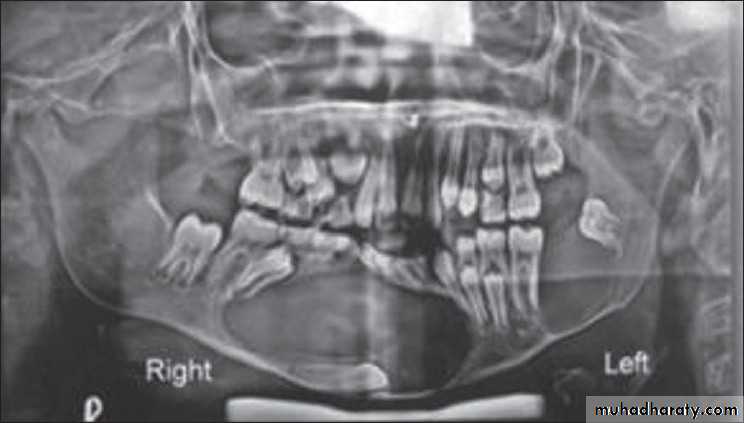

Histiocytosis-X (Langerhans cell disease):They are three manifestations produce tumour-like lesions in bone, caused by proliferation of Langerhans cells and eosinophilic leucocytes.

Radiographically :

• Multiple radiolucent areas in the interdental & interradicular bone.

• teeth seem to hang in air. Exfoliation of teeth & teeth germ are common, ulceration of overlaying mucosa.

• Multiple radiolucent foci seen in the skull & long bone of the skeleton, lesion in the skull give appearance of geographic map , with skull enlargement .

• Histiocytosis-X

• Eosinophilic Granuloma (2nd-3rd decade of life).• Hand-Schüller-Christian disease (1stdecade of life).

• Letterer-Siwe disease (before 2 years of age).